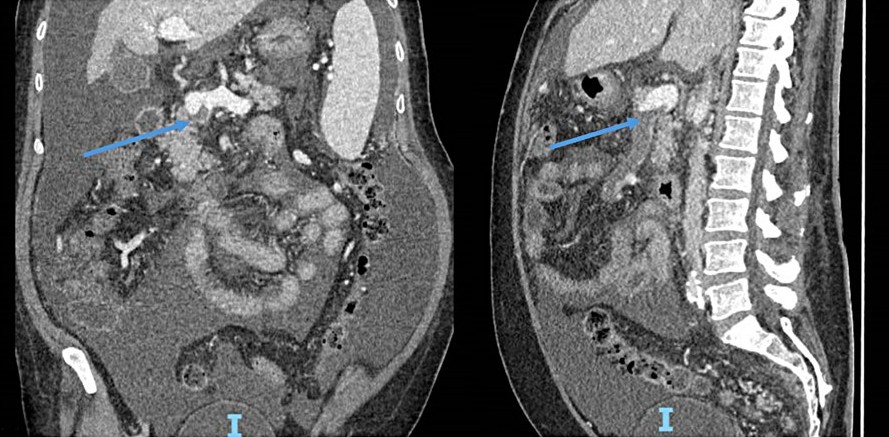

• Successful Endovascular Treatment of Acute Portal and Superior Mesenteric Vein Thrombosis in a Non-Cirrhotic Patient

Filipe Nery, Manuel Teixeira Gomes, Pedro Sousa

11-15

DOI: https://doi.org/10.60591/crspmi.555